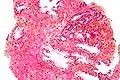

Un'entità istologica di notevole importanza è la neoplasia intraepiteliale prostatica di alto grado o PIN, caratterizzata da ampie formazioni ghiandolari con protrusioni papillari (primo elemento di distinzione con le neoplasie maligne), proliferazione intra-acinare non invasiva, anaplasia nucleare e prominenti nucleoli (in più del 10% delle cellule). Altra importante caratteristica da ricercare nella PIN è la presenza di cellule basali, assenti nel carcinoma, qui solo attenuate. La PIN è un'importante lesione che deve essere seguita nel tempo per la possibile trasformazione maligna.[60][61][62][63][64]

Neoplasia intraepiteliale prostatica di alto grado (PIN), colorazione con ematossilina-eosina, basso ingrandimento. -

Neoplasia intraepiteliale prostatica di alto grado (PIN), colorazione con ematossilina-eosina, ingrandimento intermedio. -